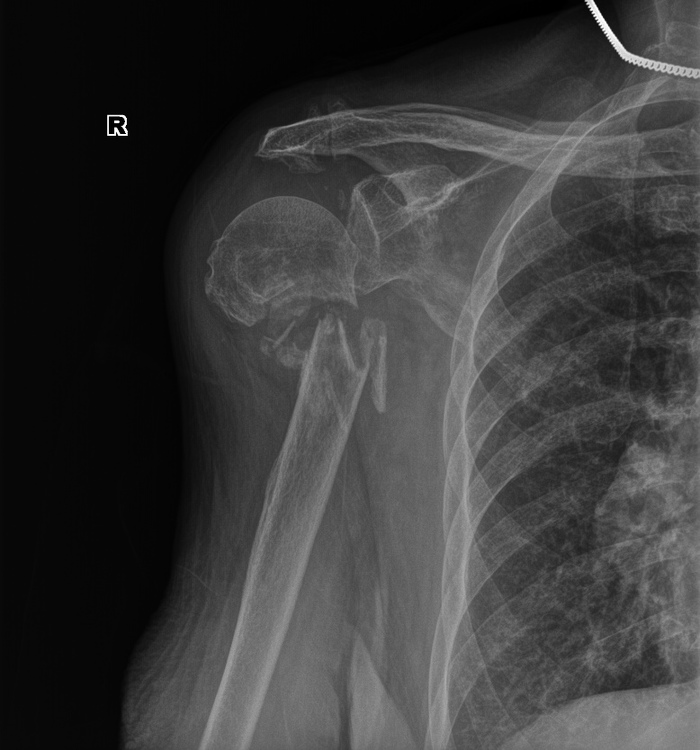

Планово для МСЭ обследовали мужчину, которому в 1983 г. в пьяной драке выстрелили из ружья в левое плечо. Плечевая кость была сломана выстрелом, перебеты все нервы (до сих пор не двигаются пальцы на руке, плохо гнется рука в плечевом суставе. Сформировался лодный сустав (т.е. кость не срослась вообще). Кость деформировна. В проекции перелома множественные металлические осколки дроби.

Так выглядит плечевая кость в прямой проекции

А так если он поднимает руку кверху - рука как бы "болтается" на этом ложном суставе.